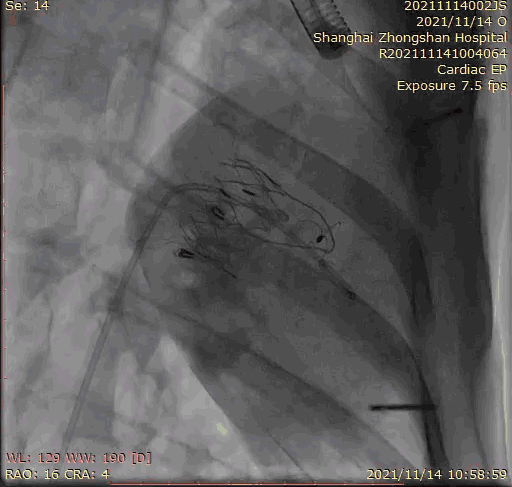

本次臨床前研究經(jīng)右側(cè)頸靜脈置入LuX-Valve Plus輸送系統(tǒng)可調(diào)彎鞘管,在DSA及超聲引導(dǎo)下將人工三尖瓣瓣膜植入到原有三尖瓣位置,利用獨(dú)特的錨定技術(shù)將人工瓣膜支架可靠固定在預(yù)定的位置。

上海中山醫(yī)院葛均波院士、錢菊英院長(zhǎng)、周達(dá)新教授、潘文志教授、潘翠珍教授、李偉教授共同完成此次臨床前研究。術(shù)后葛均波院士對(duì)Lux-Valve Plus的器械操作性能給予了高度評(píng)價(jià),DSA和超聲影像也顯示出在本次研究中Lux-Valve Plus的安全性和有效性俱佳。

Lux-Valve是全球第一款具有我國(guó)完全自主知識(shí)產(chǎn)權(quán)的經(jīng)導(dǎo)管介入三尖瓣置換系統(tǒng),利用前瓣夾持及室間隔錨定的復(fù)合方式進(jìn)行瓣膜裝置的固定,不依賴瓣環(huán)徑向支撐力,同時(shí)采用自適應(yīng)復(fù)合裙邊材料,有效的貼合密封柔軟的三尖瓣瓣環(huán),針對(duì)于三尖瓣返流的患者有優(yōu)異的療效。Lux-Valve Plus采用全新的經(jīng)血管輸送系統(tǒng),經(jīng)頸靜脈入路創(chuàng)傷更小,可以進(jìn)一步降低手術(shù)風(fēng)險(xiǎn)。相信在后期正式臨床研究開展中,Lux-Valve Plus必定會(huì)為更多的三尖瓣反流患者帶來福音。